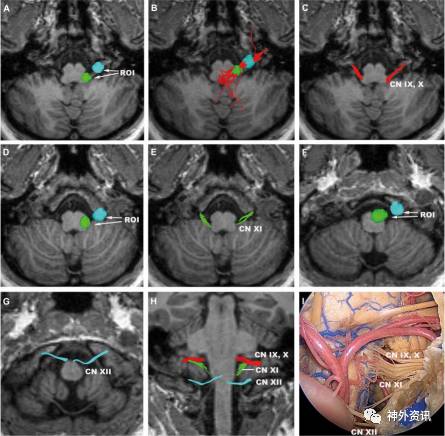

图9. 后组颅神经。A.ROI置于舌咽神经和迷走神经的颈静脉孔处和橄榄后沟上1/3;B.分割前的舌咽神经和迷走神经(轴向位);C.分割后的舌咽神经和迷走神经(轴向位);D.ROI置于副神经的颈静脉孔处和橄榄后沟下2/3;E.副神经(轴向位);F.ROI置于舌下神经的舌下神经管处和橄榄前沟下2/3;G.舌下神经(轴向位);H.舌咽神经、迷走神经、副神经和面神经(冠状位);I.对应H图的解剖示图(正面观)。